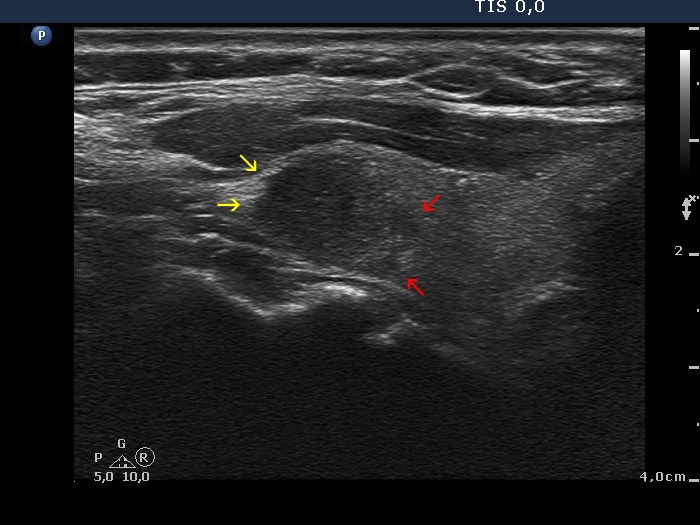

The borders of the nodule - case conp 051 (ultrasonographic picture 3b)

Left lobe, longitudinal scan. Different subtypes of irregular borders are presented. Part of the nodule has blurred borders (red arrows). The margins are spiculated and lobulated (yellow arrows), as well.